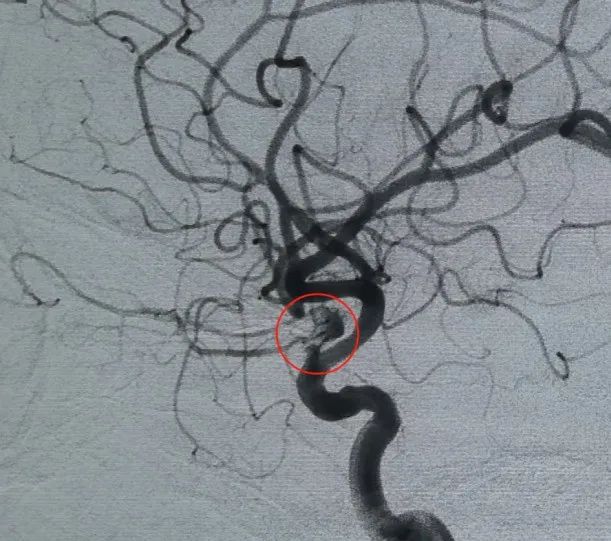

Diagnóstico: artéria carótida interna esquerda segmento C6 artéria oftálmica aneurisma

O acesso vascular foi estabelecido por punção da artéria femoral e um Perdensador®A bobina 3D de 6mm × 20 cm foi implantada pela primeira vez para formar uma cesta, alcançando a aposição estável da parede e fornecendo suporte intrassacular seguro. Isto foi seguido pela inserção de um Perdenser®6mm × 15 cm bobina 3D para interromper o fluxo sanguíneo dentro do saco filha lobulado.

Um Perfiller®3mm × 6 cm bobina expansível e um Perfiller®3mm × 2 cm bobina expansível foram então colocados para completar a oclusão do pescoço. Posteriormente, uma Nuva®Desviador de fluxo (TJED-D-5.0-16) foi entregue e implantado no pescoço do aneurisma. A angiografia de seguimento tanto na visão anteroposterior quanto na lateral confirmou excelente cobertura, boa aposição da parede e clara radiopacidade, com acentuada estagnação do contraste.